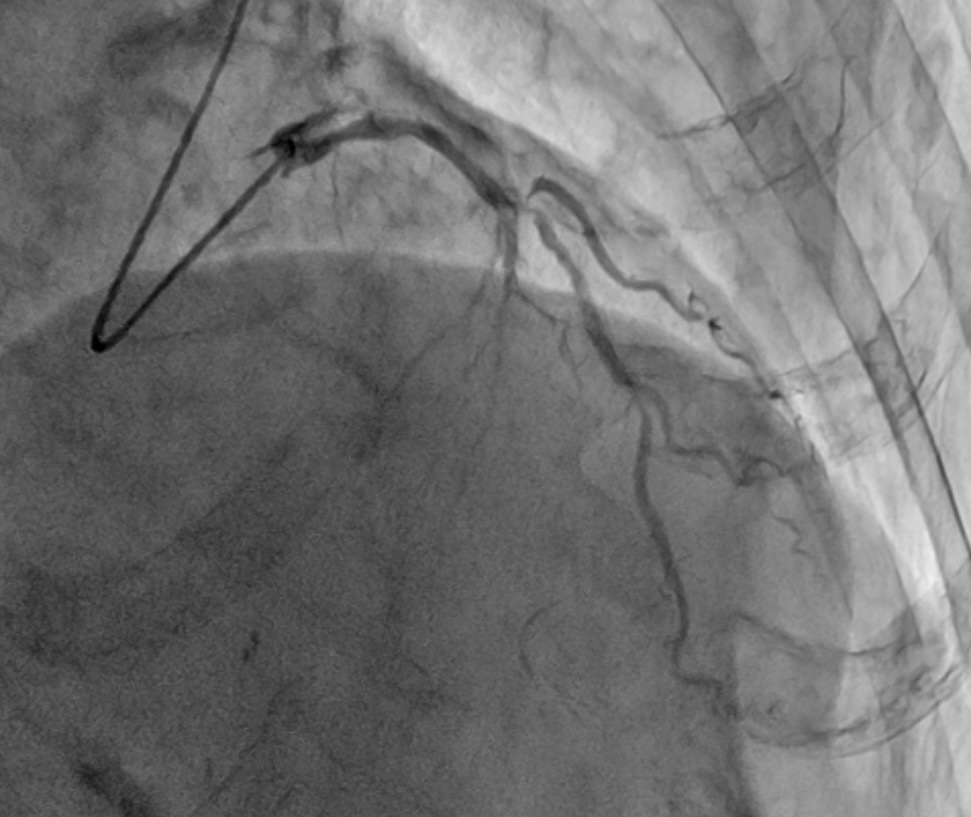

Coronary angiography revealed tandem lesions in the left anterior descending artery and a severe stenosis in the circumflex artery. The proximal left anterior descending artery was a severe bifurcation lesion (Fig 2 and 3).

We engaged a Judkins Left 4.0 6Fr guiding catheter via the left distal radial approach. Guidewires were inserted into the left anterior descending artery and diagonal branch. Tandem lesions of the LAD were inflated with a 2.25 mm scoring balloon.Then, we deployed a 2.5x16 mm drug-eluting stent using our simplified jailed balloon technique (Fig 4). This approach, without rewiring to side branches, offers key advantages.